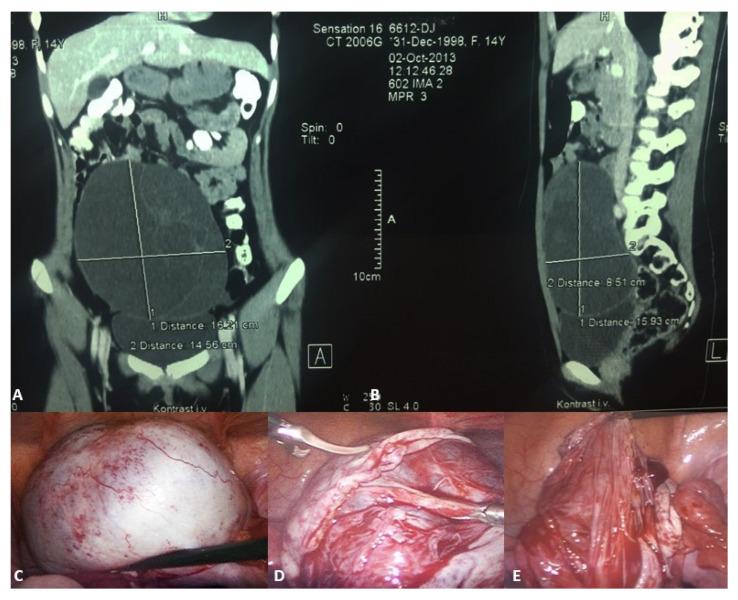

The majority of abdominal masses in female children derive from the ovaries. Ovarian masses in pediatric populations can vary from simple functional cysts to malignant neoplasms. Their incidence, clinical presentation, and histological distribution vary across age groups. In the assessment of ovarian masses in children, the primary aim is to determine the probability of malignancy, as the treatment approaches for benign and malignant lesions are significantly distinct. The primary imaging tool for evaluating ovarian cysts and masses is ultrasound, which can assess the size, location, and characteristics of masses. Magnetic resonance imaging (MRI) or computed tomography (CT) may be used for further evaluation if ultrasound findings are inconclusive or if malignancy is suspected, especially in older adolescents. Serum markers may be considered in older adolescents to help assess the risk of malignancy, though it is less useful in younger populations due to normal developmental variations. Many functional ovarian cysts, especially those detected in fetuses or infants, often resolve spontaneously without intervention. Surgical intervention is indicated in cases of large cysts that cause symptoms, or if there are concerns for malignancy. Common procedures include primarily ovarian sparing laparoscopy or laparotomy. Complications like torsion, rupture, or hemorrhage may require urgent surgical intervention. Treatment should be performed in specialized centers to avoid unnecessary oophorectomies and ensure the best possible outcome for the patient. This comprehensive review aims to provide an overview of the evaluation, diagnosis, and treatment of ovarian masses in the pediatric population. Emphasis is placed on the particularities of the lesions and their management in relation to age subgroups.

女童腹部肿块大多源于卵巢。儿科人群中的卵巢肿块种类繁多,从单纯的功能性囊肿到恶性肿瘤都有。其发病率、临床表现及组织学分布因年龄组而异。在评估儿童卵巢肿块时,主要目的是确定恶性的可能性,因为良性和恶性病变的治疗方法有显著区别。评估卵巢囊肿和肿块的主要影像学工具是超声,它可以评估肿块的大小、位置和特征。如果超声检查结果不明确或怀疑有恶性可能,尤其是年龄较大的青少年,可能会使用磁共振成像(MRI)或计算机断层扫描(CT)进行进一步评估。年龄较大的青少年可考虑检测血清标志物以帮助评估恶性风险,不过由于正常发育变异,血清标志物在年幼儿童中作用较小。许多功能性卵巢囊肿,尤其是在胎儿或婴儿中发现的囊肿,常常无需干预即可自行消退。对于引起症状的大囊肿或怀疑有恶性可能的情况,需进行手术干预。常见手术主要包括保留卵巢的腹腔镜手术或剖腹手术。扭转、破裂或出血等并发症可能需要紧急手术干预。治疗应在专业中心进行,以避免不必要的卵巢切除术,并确保患者获得最佳治疗效果。本综述旨在概述儿科人群卵巢肿块的评估、诊断和治疗。重点在于病变的特殊性及其在不同年龄亚组中的处理。